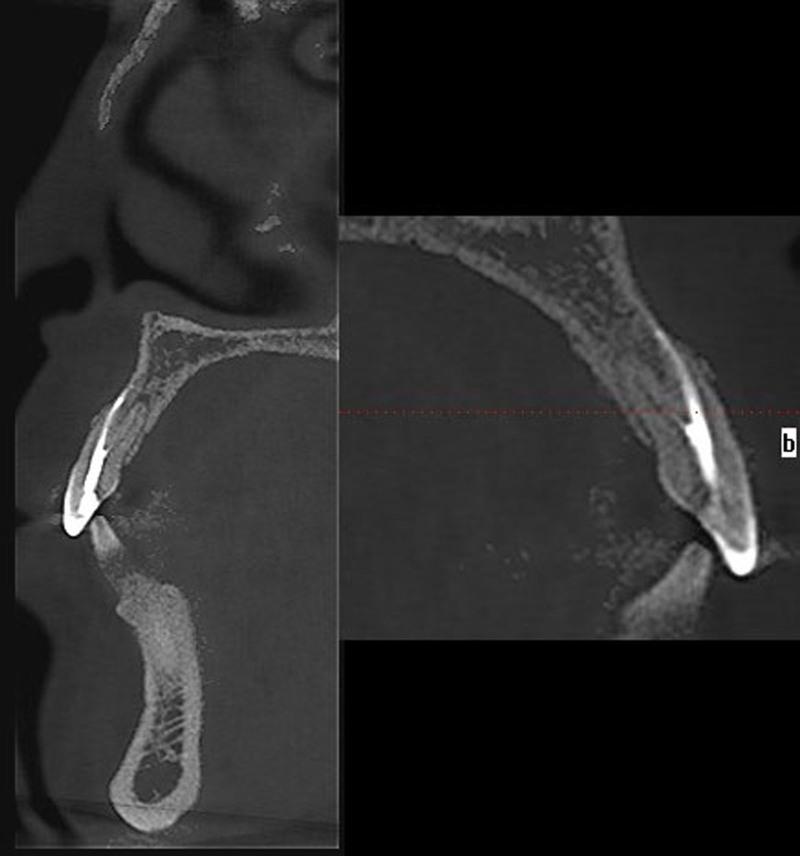

Cone beam computed tomography imaging revealed a left maxillary lateral incisor (tooth 22) with double roots and double root canals, with chronic apical periodontitis associated with the untreated palatal canal.

锥形束计算机断层扫描成像显示左上颌侧切牙(22号牙)有双根和双根管,伴有与未治疗的腭侧根管相关的慢性根尖周炎。